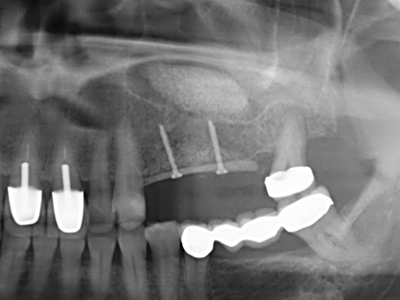

Abb. 11: Das postoperative OPTG veranschaulicht die vertikale Augmentation und Sinusbodenelevation.

Abb. 12: Nach sechs Monaten Heilungsperiode zeigt sich ein in allen Richtungen ausreichend dimensionierter, vitaler Kieferkamm.